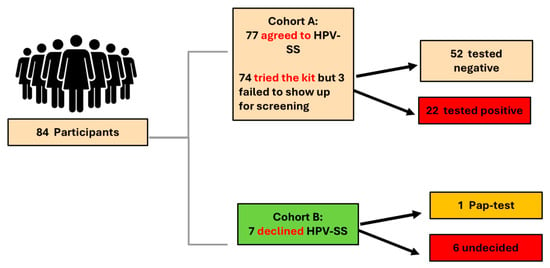

Voices from the Margins: Barriers and Facilitators to HPV Self-Sampling Among Structurally Marginalized People with a Cervix in the Greater Toronto Area and Ontario

by

Mandana Vahabi, Natasha Kithulegoda, Masoomeh Moosapoor, Aisha Lofters, Josephine Pui-Hing Wong, Abdolreza Akbarian and Jenna Hynes

Curr. Oncol. 2025, 32(6), 327; https://doi.org/10.3390/curroncol32060327 - 3 Jun 2025

Sex workers and formerly incarcerated people with a cervix face significant structural, interpersonal, and emotional barriers to cervical cancer screening, despite being at elevated risk for HPV infection. HPV self-sampling (HPV-SS) is a validated, user-directed method that has the potential to address these

Sex workers and formerly incarcerated people with a cervix face significant structural, interpersonal, and emotional barriers to cervical cancer screening, despite being at elevated risk for HPV infection. HPV self-sampling (HPV-SS) is a validated, user-directed method that has the potential to address these barriers, yet it remains excluded from Ontario’s organized screening program. This qualitative study explored the lived experiences of structurally marginalized individuals with a cervix who were offered HPV-SS as part of a mixed-methods pilot in the Greater Toronto Area. Five virtual focus groups were conducted with 34 participants, including both those who used the HPV-SS kit and those who declined it. Using inductive thematic analysis, we identified barriers to traditional screening including fear, stigma, mistrust of healthcare providers, logistical constraints, and a lack of accessible information. HPV-SS was widely described as more acceptable, empowering, and emotionally manageable, offering participants autonomy, privacy, and control over their care. Concerns included swab design, uncertainty about correct use, and unclear follow-up after positive results. Participants offered concrete, community-informed recommendations to improve HPV-SS implementation, including opt-in distribution models, gender-affirming language, and trauma-informed educational materials. The findings highlight the urgent need to integrate HPV-SS into organized screening programs to advance equitable access to cervical cancer prevention for marginalized populations.

(This article belongs to the Special Issue Action and Impact: Prevention and Screening Strategies Contributing to the Elimination of Cervical Cancer)

Figure 1